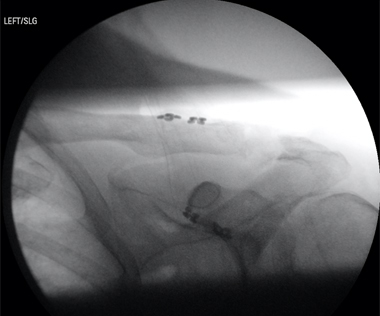

AP chest radiography should be performed as part of initial trauma series. On a nonrotated chest radiograph, assessment of lateral scapular displacement can be performed by measuring distance between a midline thoracic spinous process and the medial borders of the scapula on both the injured and uninjured sides. A difference > 1 cm is diagnostic of scapulothoracic dissociation [1, 5]. Orthogonal radiographs of any suspected upper extremity fracture or dislocation should also be obtained. Immediate Vascular imaging with CT angiography is recommended in patients with suspected scapulothoracic dissociation [2]. CT myelography, MRI, or EMG studies can be used for evaluation of brachial plexus injuries. Nerve studies are usually reserved for at least 3 weeks after injury to assess degree of recovery, if any.